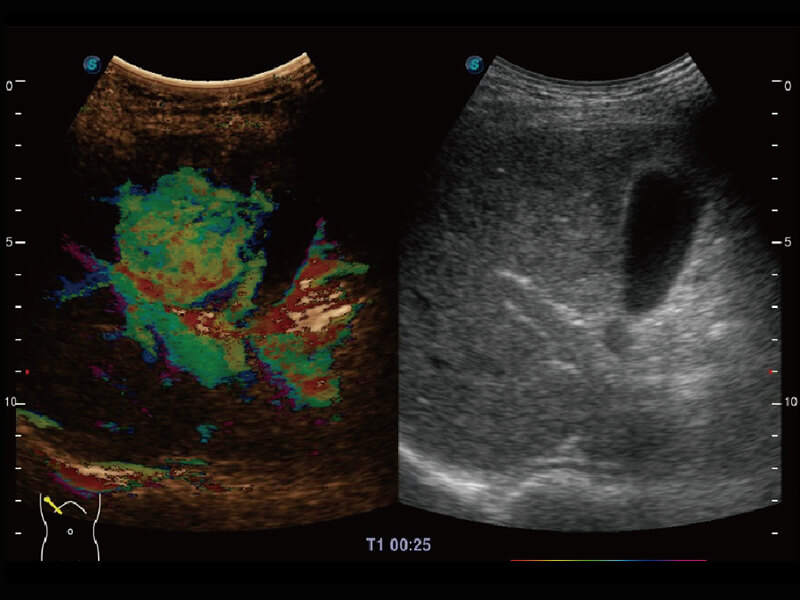

成像功能

S60探头工艺,从前端信号处理每一个环节采集无损声学数据,真实还原组织原貌,再现解剖细节。